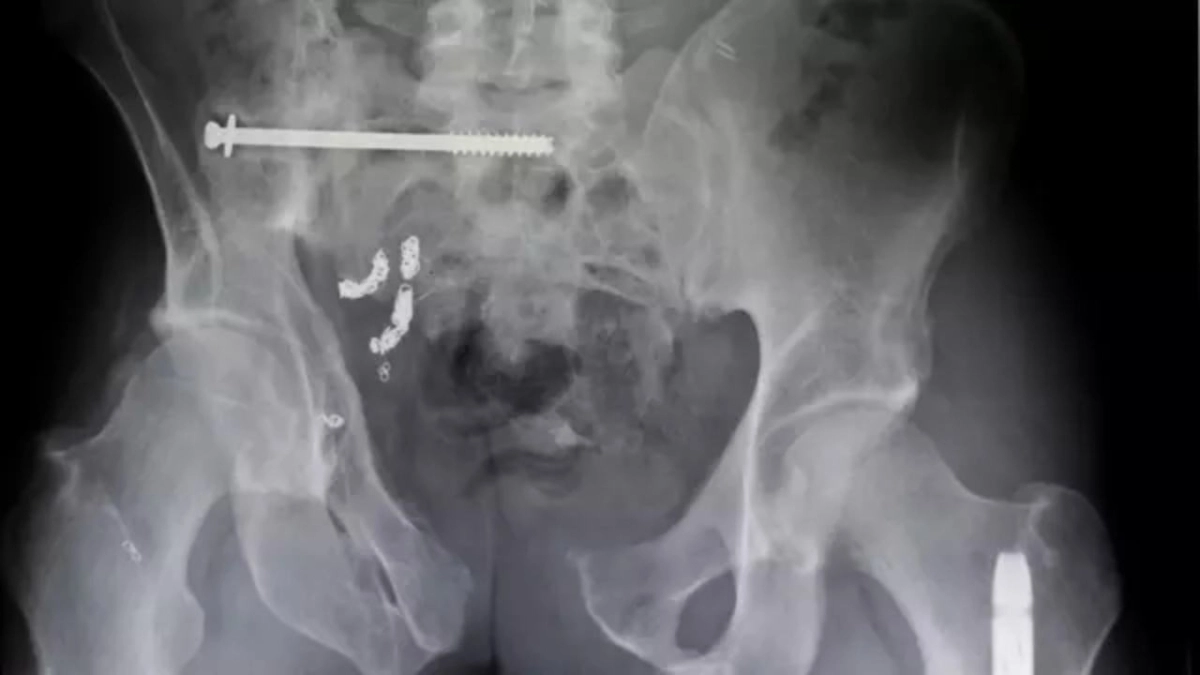

Μπορεί να ακούγεται σαν αστικός μύθος, όμως τα στοιχεία είναι αμείλικτα. Σχεδόν 4.000 άνθρωποι στις ΗΠΑ νοσηλεύονται κάθε χρόνο λόγω ξένων αντικειμένων που σφηνώνουν στον πρωκτό τους, ενώ στη Βρετανία το κόστος για το NHS ξεπερνά τα 3 εκατ. λίρες.

Το φαινόμενο καταγράφεται εδώ και δεκαετίες,